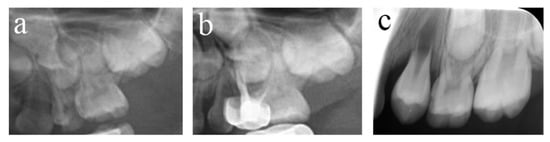

Figure 3.

#84 was treated with pulpectomy and filled with ZOE under DGA. The follow-up period was 34 months (31-month-old male child) (a) Two weeks after the operation, the radiographic showed that the filling in the distal roots was underfilled. (b) Thirty-four months after treatment, #84 was lost early, but a portion of the ZOE particles remained. The pulpectomy in #84 failed.

Figure 4.

#51, #61, and #62 received pulpectomies under DGA with a 12-month follow-up period (57-month-old female child). (a) Preoperative radiograph and #61 revealed periapical radiolucency. (b) Two weeks later, the postoperative radiograph showed underfilling in #61 and optimal filling in #51 and #62. (c) Radiograph taken 12 months postoperatively showing nothing abnormal about #62 and a periapical radiolucency surrounding the root apical of #51. Moreover, a radicular cyst occurred surrounding the apical root of #61, and the eruption direction of #21 was altered. Pulpectomies in #62 succeeded but failed in #51 and #61.